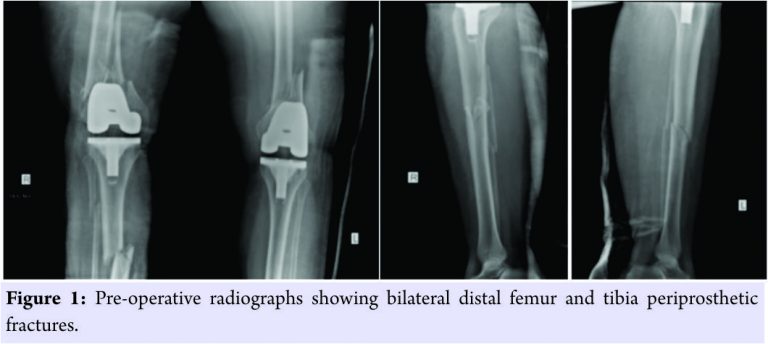

A 64-year-old female operated with bilateral primary TKA 3 years back came with ssimultaneous bilateral distal femur (Bilateral Type IIB Rorabeck) and tibia (Bilateral Type IIIB Felix) periprosthetic fractures following road traffic accident. The patient was admitted and evaluated with radiographs for further management.

She is a known case of systemic hypertension under treatment and control. After necessary fitness, the patient was operated on both sides in two stages, at a time one limb was operated using swashbuckler approach for distal femur and anterolateral approach for tibia using locking plates due to osteoporosis. Bone graft was not required based on intraoperative findings and lack of comminution. Patient was given routine antibiotic and DVT prophylaxis and was mobilized from the 1stpost-operative day with static quadriceps and passive range of motion exercises. Calcium and Vitamin D3 supplementation given postoperatively and bisphosphonates were not considered. For the 1st6 weeks, the patient was non-weight-bearing following which weight-bearing as tolerated advised, at the end of 3 months as the radiographs show signs of healing patient was advised full weight-bearing. Bony union achieved in 4th post-operative month without any complication.